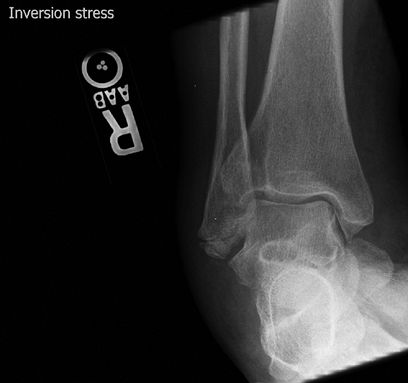

Stress Views of the Ankle

These give more functional information than MRI about

ligamentous laxity and are useful in planning treatment for unstable

ankles. It is important to have the other side for comparison.

![]() |

|

Figure 26 AP ankle with varus stress.